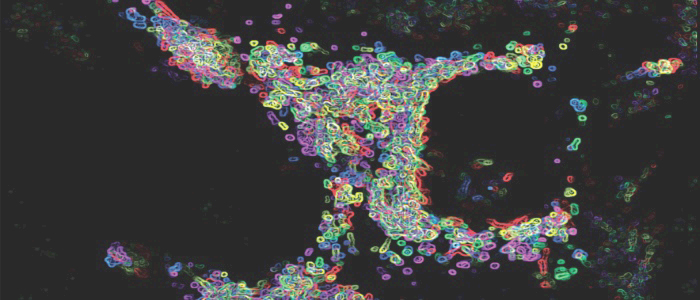

Scientists create leukaemia online tool to aid global search for cure

Tue, 09 May 2017 15:17:00 BST